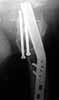

A male 56 years old was operated in Aug 2003 - valgus osteotomy performed because of delayed admission with neck fracture (2 months) images 1,2. Smoker, no other major medical problem.

Image 2